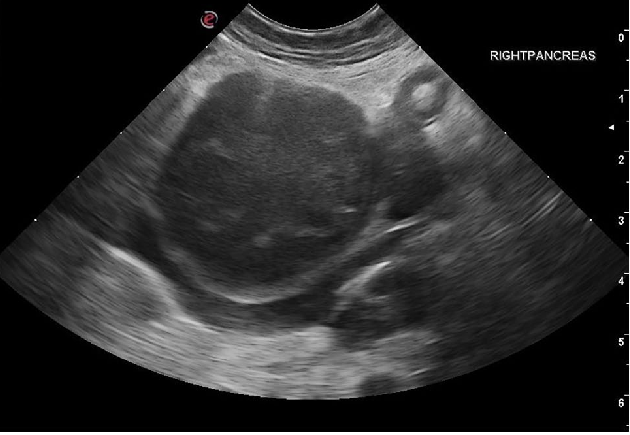

보통 고양이 췌장염에서 진균에 해당하는 캔디다 등의 감염 가능성은 높게 생각하지 않는데

이 증례의 경우 췌장부에 종괴성의 병변이 있어 종양을 감별하기 위해 초음파 유도하에 세포 검사를 진행하였고

캔디다증으로 증명된 케이스이다.